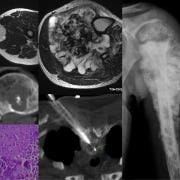

66-years old man presented with a mass in the spleen involving the tail of the pancreas.

Findings: Large splenic mass involving tail of pancreas

Lesion Biopsied: Splenic mass

Size of Lesion: > 30 mm

Diagnosis: Non-Hodgkin’s lymphoma, large B-cell type